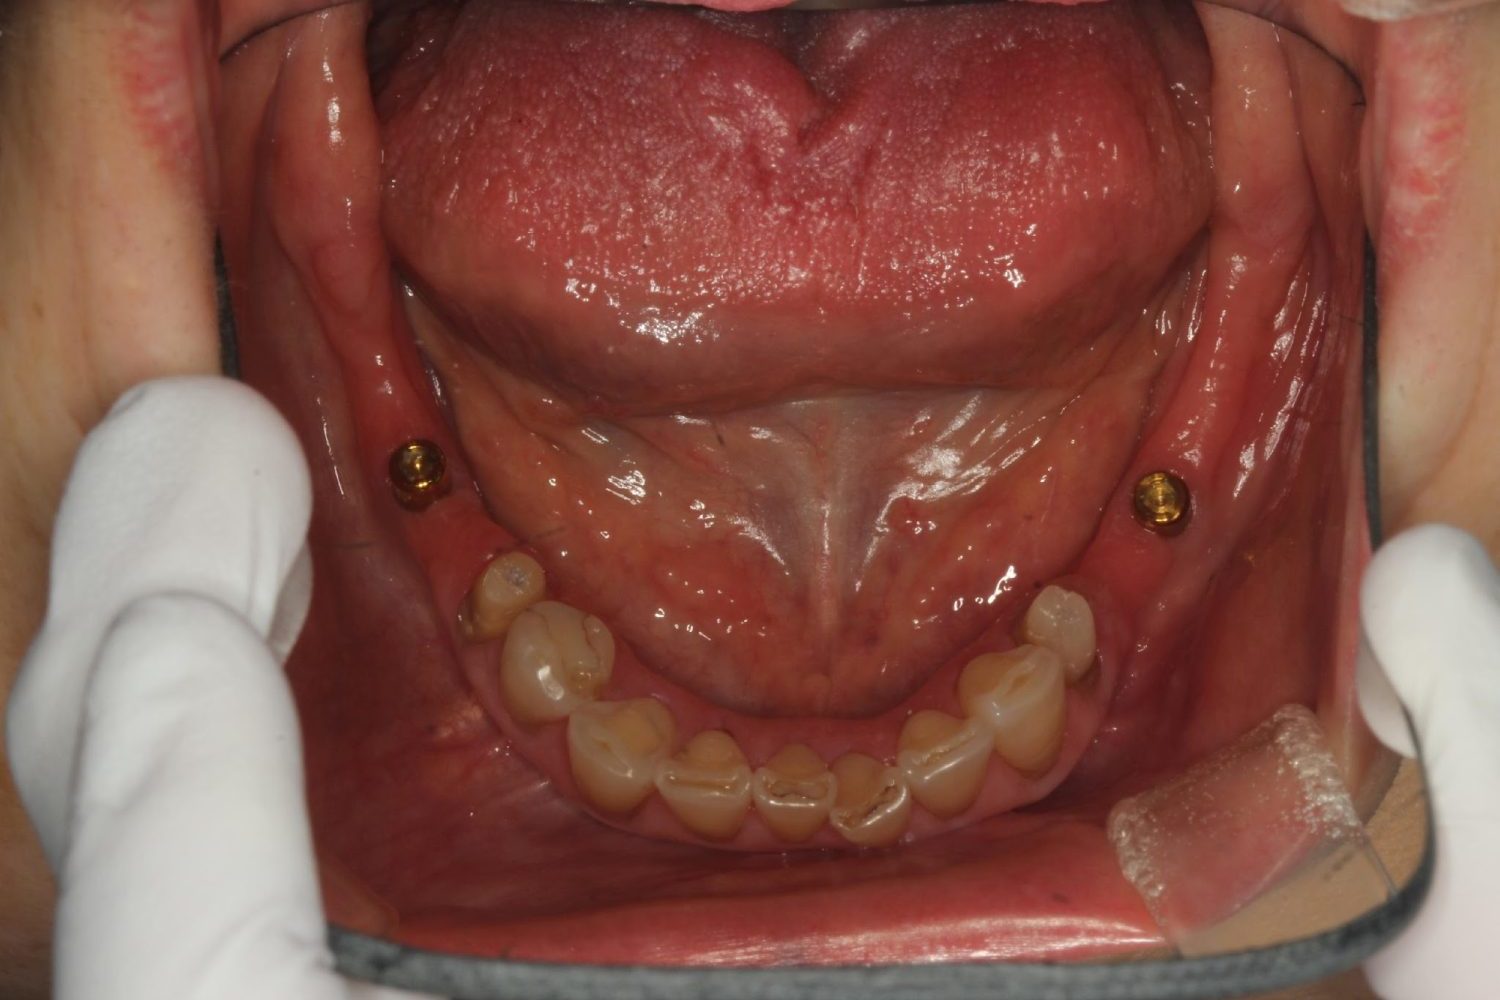

インプラント治療の症例紹介⑩

Before

治療中

After

主訴

入れ歯を入れたい

治療内容

欠損部に上顎に3本、下顎に2本インプラント埋入を行い、インプラントオーバーデンチャーを装着しました。

治療費

2,406,800 円(税込)

治療期間

29ヶ月

通院回数

22回数

想定されたリスク

※義歯を安定させるためのインプラントなので、顎堤が吸収等起こし裏装が必要になる可能性がありました。

濱 仁隆先生

浜歯科

上下義歯ともインプラントを用い義歯安定を行った症例です。